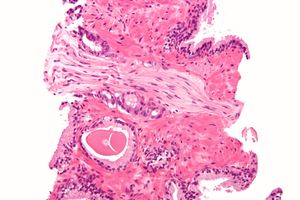

A diagnosis of prostate cancer requires a biopsy of the prostate. Prostate biopsies are typically taken by a needle passing through the rectum or perineum, guided by transrectal ultrasound imaging, magnetic resonance imaging (MRI), or a combination of the two.[10][8] Ten to twelve samples are taken from several regions of the prostate to improve the chances of finding any tumors.[8] Biopsies are examined under a microscope by a pathologist, who determines the type and extent of cancerous cells present. Cancers are first classified based on their appearance under a microscope. Over 95% of prostate cancers are classified as adenocarcinomas (resembling gland tissue), with the rest largely squamous-cell carcinoma (resembling squamous cells, a type of epithelial cell) and transitional cell carcinoma (resembling transitional cells).[11]

Next tumor samples are graded based on how much the tumor tissue differs from normal prostate tissue; the more different the tumor appears, the faster the tumor is likely to grow. The Gleason grading system is commonly used, where the pathologist assigns a number from 1 (most similar to healthy prostate tissue) to 5 (least similar) for the most common pattern observed under the microscope, then does the same for the second-most common pattern. The sum of these two numbers is the Gleason score.[11] The total scores of 2 through 5 are no longer commonly used in practice, making the lowest score 6, and the highest score 10. Scores are commonly grouped into Gleason grade groups: a score of 6 or lower is Gleason grade group 1; a score of 7 with the first number (from the most common pattern) 3 and the second number 4 is grade group 2; the reverse – first number 4, second number 3 – is grade group 3; a score of 8 is grade group 4; a score of 9 or 10 is grade group 5.[11] Higher Gleason scores and higher grade groups represent cancer cases likely to be more aggressive with worse prognosis.[11]